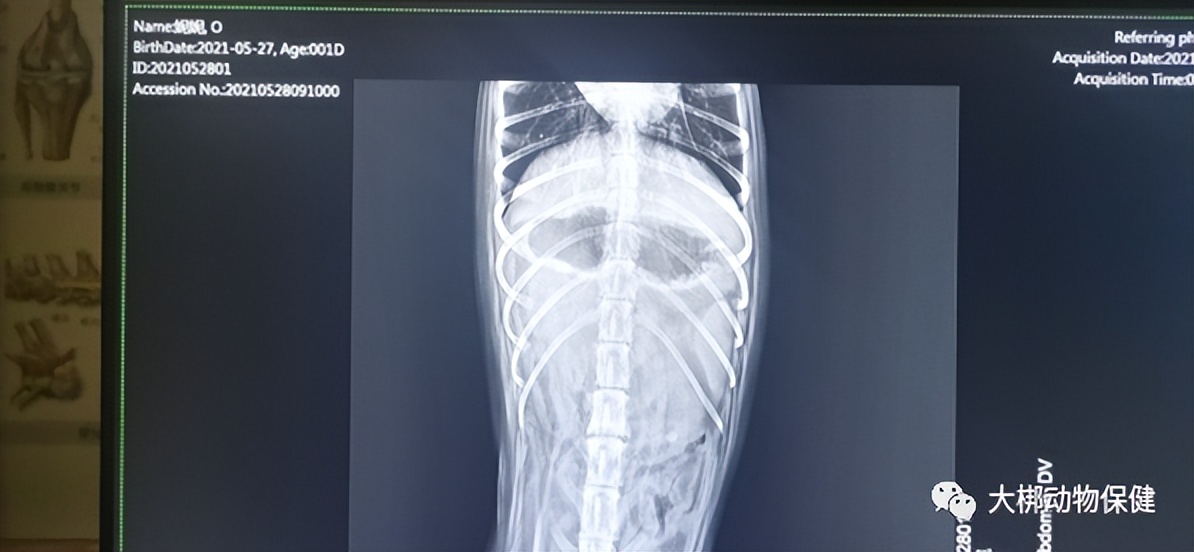

医生进行一般性检查发现: 触诊腹部紧张有疼痛感,结膜炎颜色正常、口腔颜色偏白,肌肉状态良好,对食物无兴趣,喜卧不动。血常规无异常,犬C反应蛋白轻度升高,犬胰腺炎指标升高,DR影像显示胃肠气体,无高密度异物。